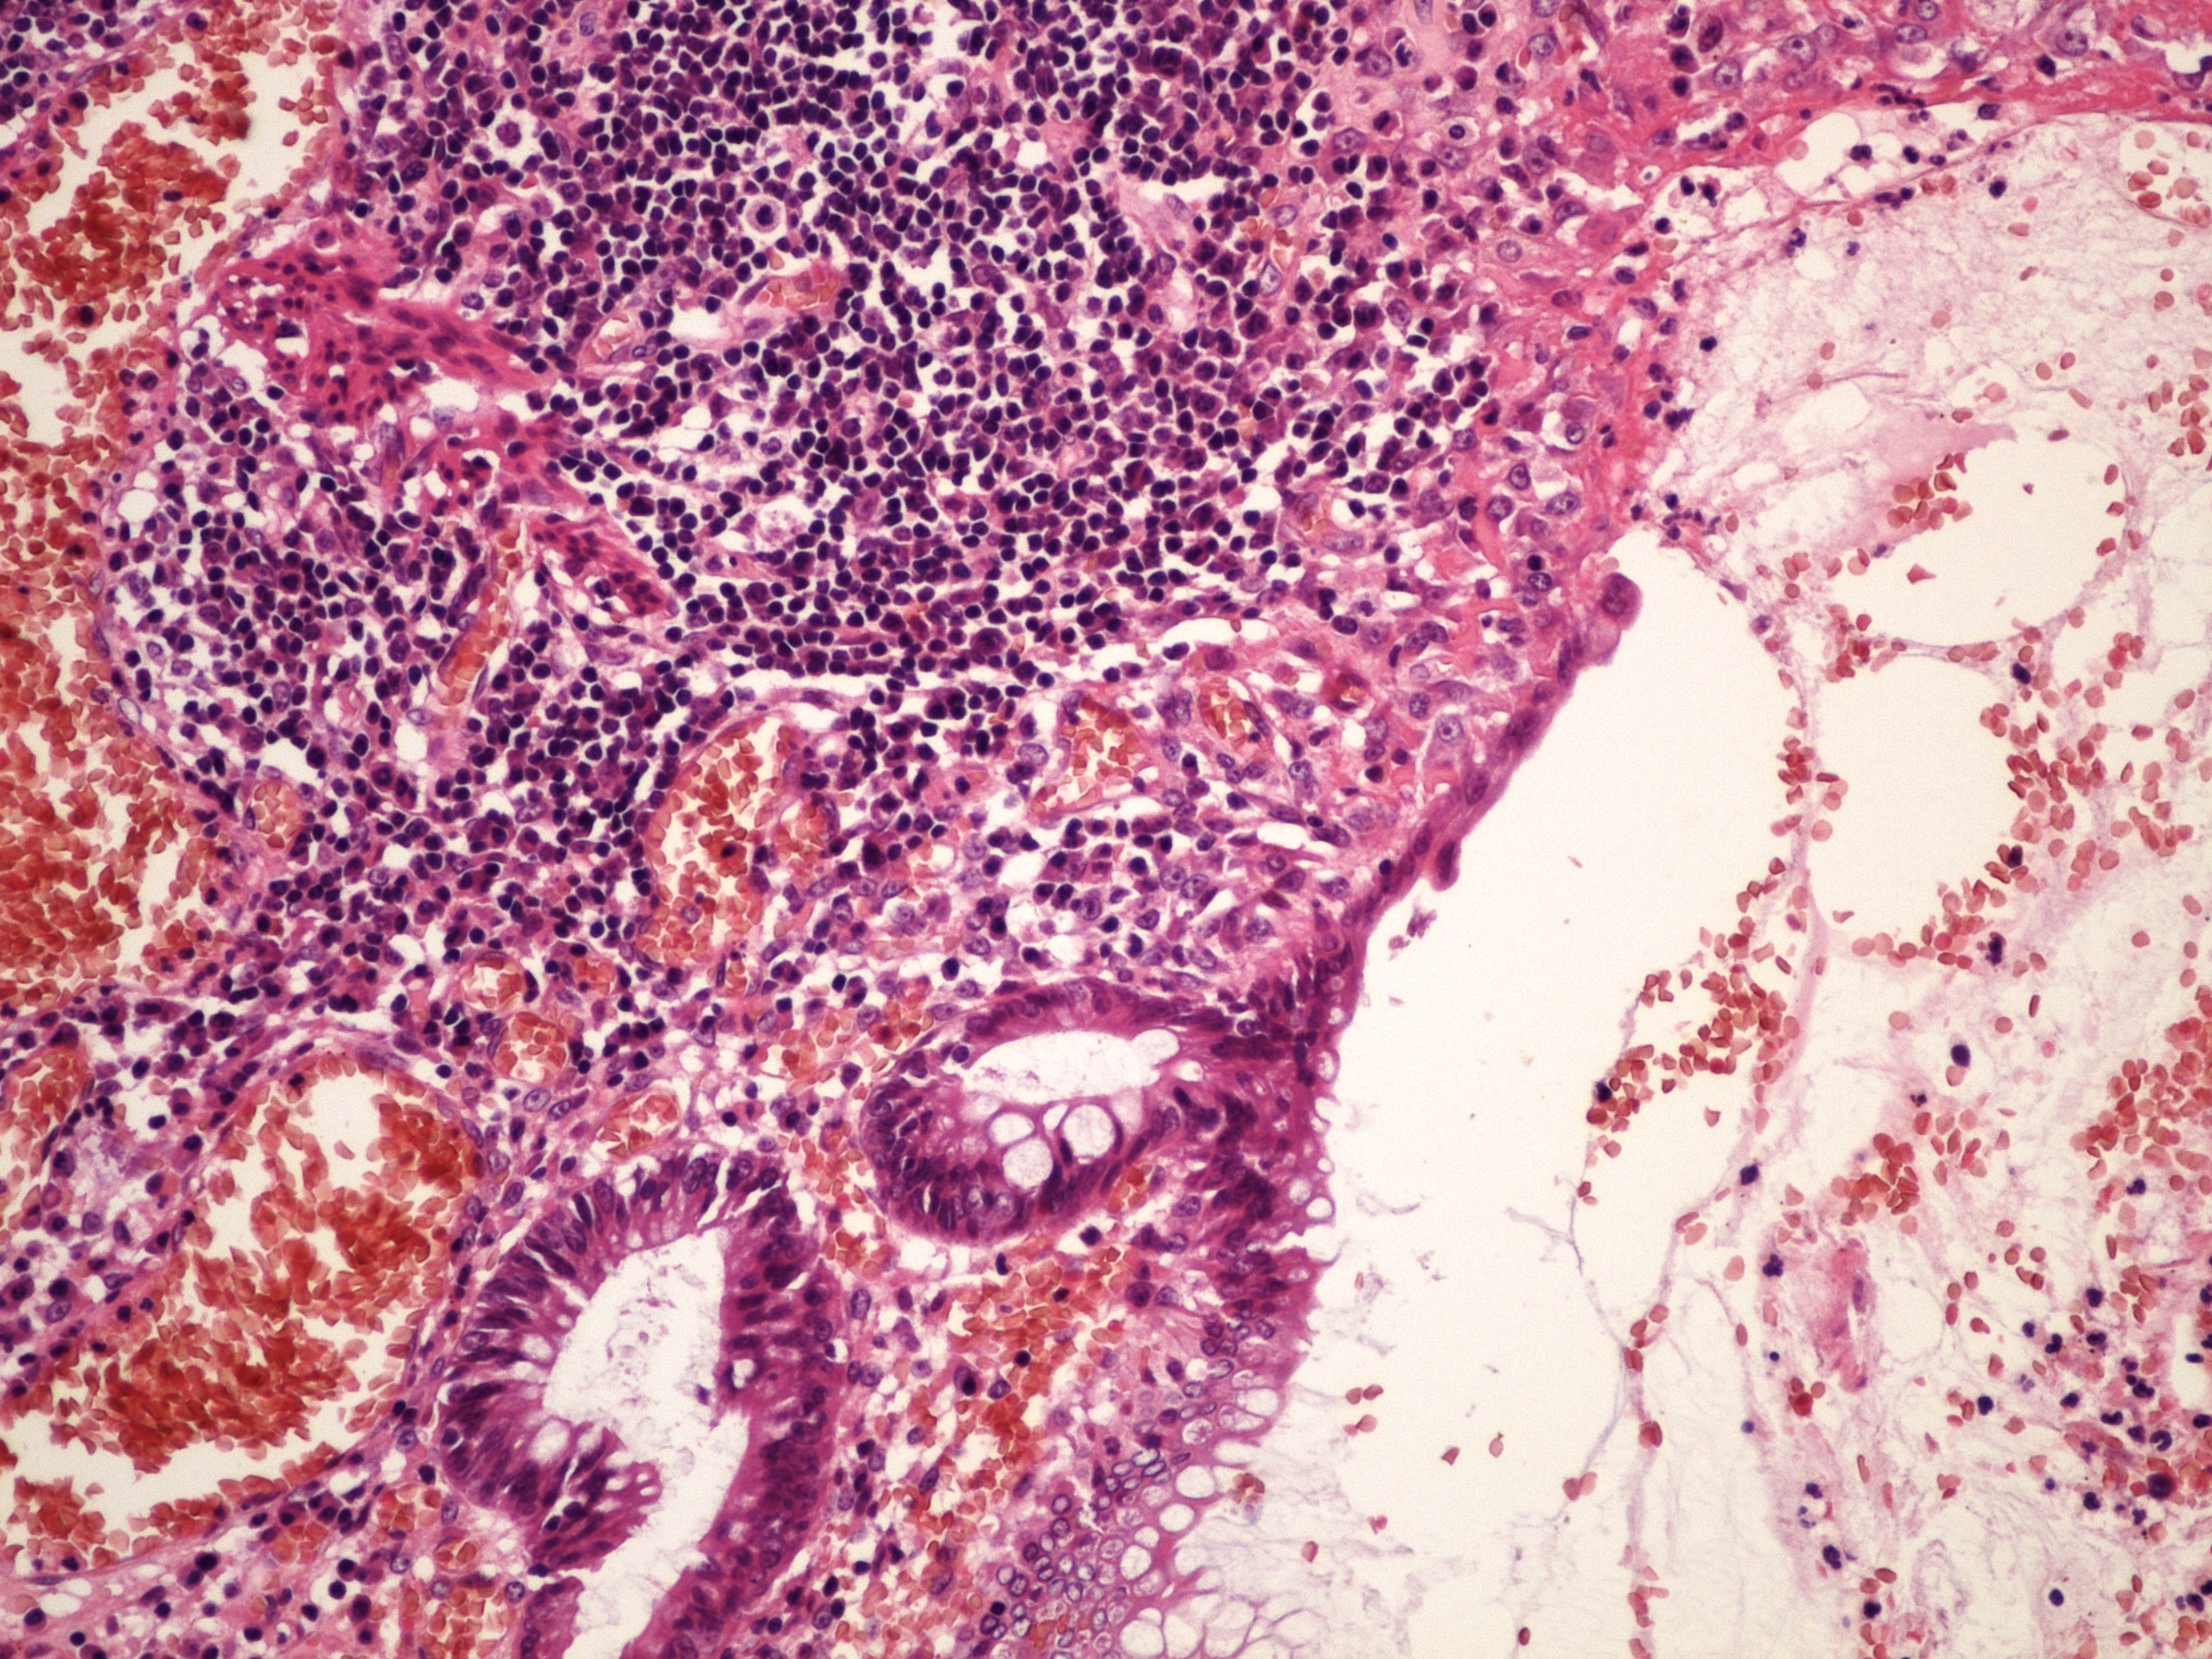

Preparát č.1 a č.2 - ulcerósní kolitis

Struktury

- zánětlivý infiltrát; nezasahuje transmurálně